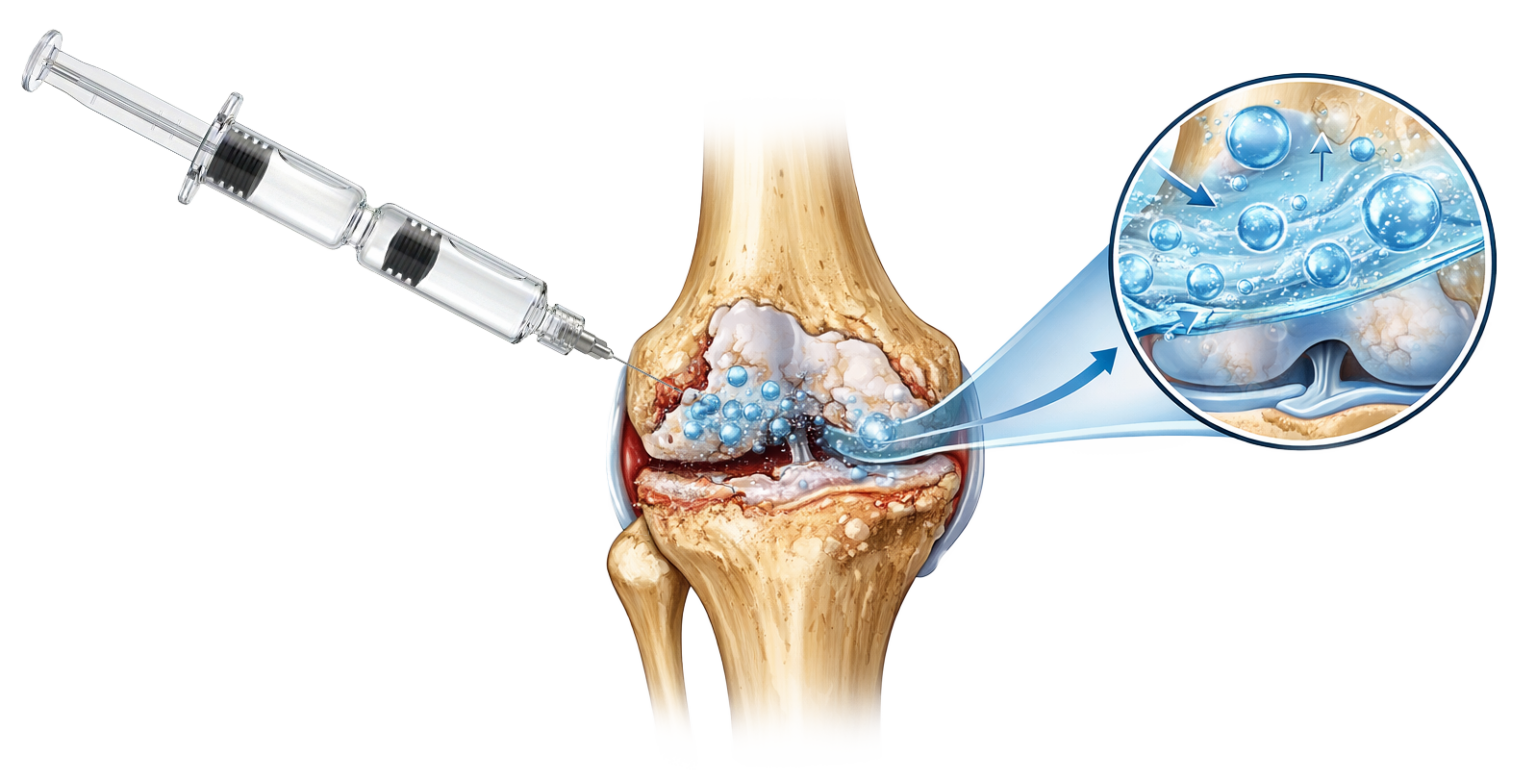

Wie wirkt RenehaVis?

Injektion statt Operation

Rund 200.000 künstliche Kniegelenke werden jährlich in Deutschland eingesetzt, um Schmerzen bei Arthrose zu behandeln. Gleichzeitig zeigen Studien, dass operative Eingriffe wie Arthroskopien oder Gelenk-Ersatz teilweise früher erfolgen als dies medizinisch notwendig wäre.

Eine mögliche Therapieoption ist die Injektion von Hyaluronsäure. Mit RenehaVis steht hierfür eine Doppelkammerspritze zur Verfügung, die zwei Hyaluronsäuren mit unterschiedlicher molekularer Struktur kombiniert. In einer Studie (letzte Seite) wurden 200 Patienten mit Kniearthrose durch RenehaVis behandelt. Ergebnis: Die Patienten berichteten von einer signifikant höheren Zufriedenheit im Vergleich zum Einsatz von Einkammerpräparaten.

Die spezielle Doppelkammerspritze ermöglicht die getrennte Applikation zweier Hyaluronsäure-Formen in einem Behandlungsschritt

- RenehaVis wird intraartikulär injiziert.

- Anwendung unter sterilen Bedingungen

- Optional ultraschallgestützt

- Einmalige Injektion gemäß Indikation

Doppelte Technologie – synergistische Wirkung

RenehaVis kombiniert:

- Hochmolekulare, nicht-vernetzte Hyaluronsäure

– Sofortige Verbesserung der Gleitfähigkeit - Vernetzte Hyaluronsäure

– Längere intraartikuläre Verweildauert

Vorteile gegenüber einheitlich vernetzter Hyaluronsäure:

- Optimierte Anfangsviskosität

- Bessere Verteilung im Gelenk

- Kombination aus schneller Wirkung und verlängerter Stabilität

- weniger Injektionen

Die Kombination aus niedrig- und hochmolekularer Hyaluronsäure verbessert sowohl die Gleitfähigkeit als auch die Stoßdämpfung – und zeigte in einer Studie eine überlegene klinische Wirksamkeit. (1)